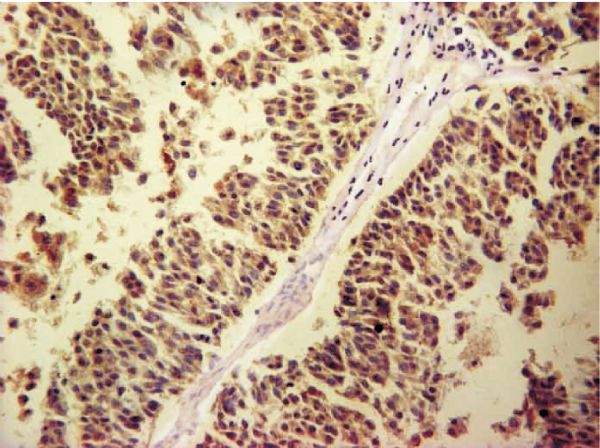

Bin HAO, Changwei LIU, Huixiang LI

The mRNA and protein expression of phosphatase of regenerating liver 1 (PRL-1) and phosphatase of regenerating liver 3 (PRL-3) in transitional cell carcinoma of bladder (BTCC) and normal epithelia of bladder was investigated, and the relationship between the BTCC and pathological changes was clarified. The expression of PRL-1 and PRL-3 mRNA was detected by using reverse transcription polymerase chain reaction (RT-PCR) in 30 cases of BTCC and 10 cases of normal bladder, and the expression of PRL-1 and PRL-3 protein was checked by using immunohistochemistry in 30 cases of BTCC and 15 cases of normal bladder. The expression levels of PRL-1 and PRL-3 mRNA and protein were higher in BTCC than those in normal bladder epithelia (P<0.05). The increased expression of PRL-1 and PRL-3 mRNA and protein was detectable in deep invasion and metastasis of BTCC (P<0.05). There was no correlation between the expression of PRL-1 and PRL-3 and gender, age or recurrence of BTCC (all P>0.05). A significantly positive correlation was found between PRL-1 and PRL-3 in BTCC (P<0.05). PRL-1 and PRL-3 are expressed consistently and may contribute to the growth, differentiation, invasion and metastasis of BTCC.